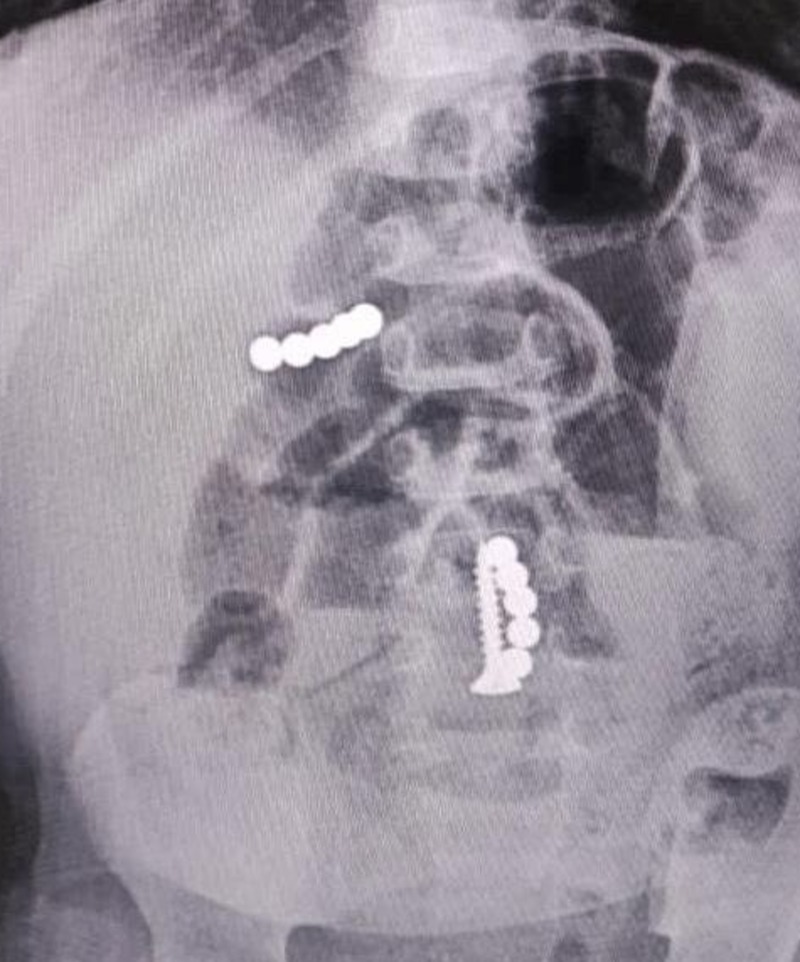

Специалисты клинической больницы скорой медпомощи Ставрополя получили патент на прорывное изобретение в области лечения травм спинного мозга.

Хирурги получили исключительное право на способ лечения травм спинного мозга с восстановлением его функций конъюнгатом ПЭГ-хитозана. Срок действия патента — до 2042 года.

Как пояснил один из разработчиков Михаил Лебенштейн-Гумовски, это химическая смесь двух компонентов, которые взаимно усиливают друг друга. Экспериментальный гель помогает восстанавливать поврежденную структуру важнейшего органа.

Разработанная методика стала прорывом в области спинальной нейрохирургии. Способ лечения введут в клиническую практику для пациентов с травмами спинного мозга.